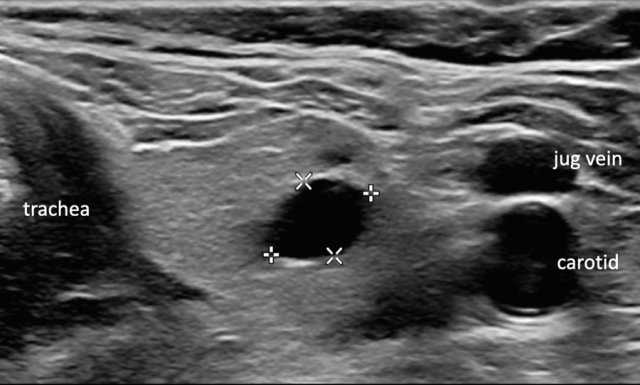

Cystic lesions or lesions that are almost completely cystic are benign and no further points will be added  (TI-RADS 1).

Cyst

Here a typical cyst.

No further evaluation is needed.